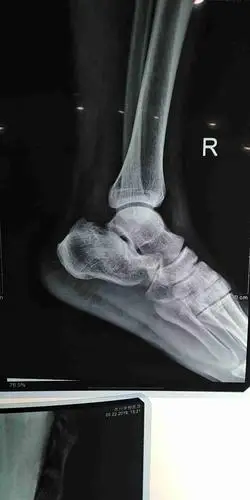

脚跟粉碎性骨折.那位大神会看x.ct片子?帮我看看,骨折了吗?治疗方案.

踝关节 开放性 粉碎性骨折伴脱位

请问右跟骨粉碎性骨折怎么治疗

问:跟骨粉碎性骨折.没有手术.这是两个月的复查片.